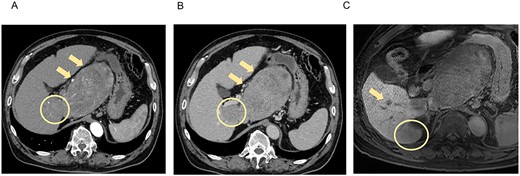

CT and MRI showed weakened stained areas of the S1 and S6/7 tumors with internal lipiodol deposition and poor enhancement. Positron emission tomography-CT showed no abnormal fluorodeoxyglucose accumulation suspicious for lymph node metastasis or distant metastasis (Fig. 2). The patient was evaluated as having stable disease in the Response Evaluation Criteria in Solid Tumors (RECIST) and a partial response in the modified RECIST.

CT and MRI after LEN plus TACE. Axial enhanced CT shows weakened stained areas of the tumors in S1 (A, B, arrow, circle) and S6/7 with internal lipiodol deposition and poor enhancement (A, B, arrowhead), with weakly enhanced areas at the margins that are suspected to be viable lesions. MRI reveals lesions with extensive internal hemorrhage because of treatment in S6/7 (C, circle) and S6 (C, arrow). Positron emission tomography-CT shows the mass lesions with abnormal accumulation in liver S1 (SUV max 11.7; D, arrow) and S6/7 (SUV max 4.2; D, arrowhead). S, segment; SUV, standardized uptake value.